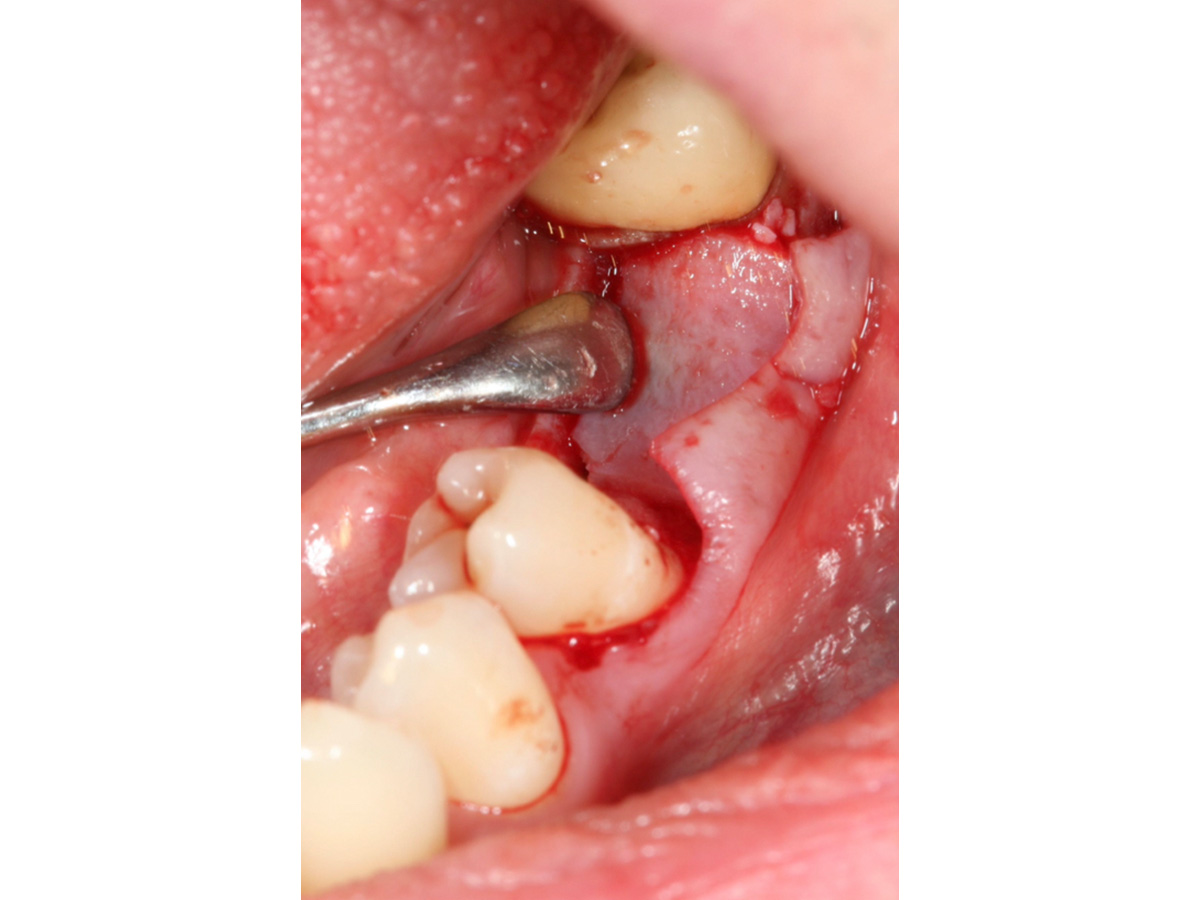

Nach Implantation wurde die zugeschnittene Bone Lamina positioniert und mit Pins fixiert, die Situation danach ist in Abb. 5 zu sehen. Mit dem Instrument wird demonstriert, dass eine „Tasche“ geschaffen wurde, die in Abb. 6 mit mp3® Knochengranulat aufgefüllt wird. Abb. 7 stellt dar, wie die Bone Lamina über den Kopf des Implantates auf den lingualen Anteil des Kieferkammes positioniert wird.

Positionierung der Bone Lamina auf den lingualen Anteil des Kieferkammes.

Abbildung 7